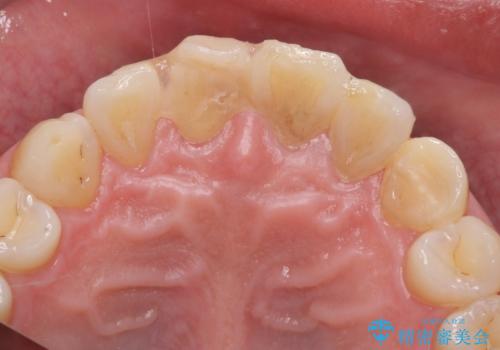

転んで前歯が欠けてぐらぐらに 歯の神経も死んでしまった

- 転倒して前歯を強打してかけてしまった、ぐらつくとのことで来院。

応急でみてもらった歯科医院で隣の歯と接着剤で留めてもらったとのこと。

歯の神経の状態を見たところ、前歯3本とも神経が死んでしまっていました。

また、左上犬歯の詰め物は途中で脱離し、セラミックでの修復をご希望されたため、一緒に治療しました。

根の治療を行い、ぐらつきに関しては様子を見て連結をするとのお話をさせていただきました。

結果ナイトガードの使用によりぐらつきはだいぶ回復してきたため連結はしていません。